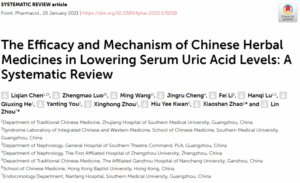

漢方生薬56種類と漢方処方52種類を研究した10編の臨床試験と、186編の疾患モデル動物試験(in vivo)および試験管試験(in vitro)の論文を総合すると、漢方薬が複数のターゲットと経路を通じて血中尿酸値を低下させることが明らかになりました。主な機序は尿酸合成、尿酸輸送、炎症、腎線維化、酸化ストレスに関連しており、一つずつ見ていきましょう。